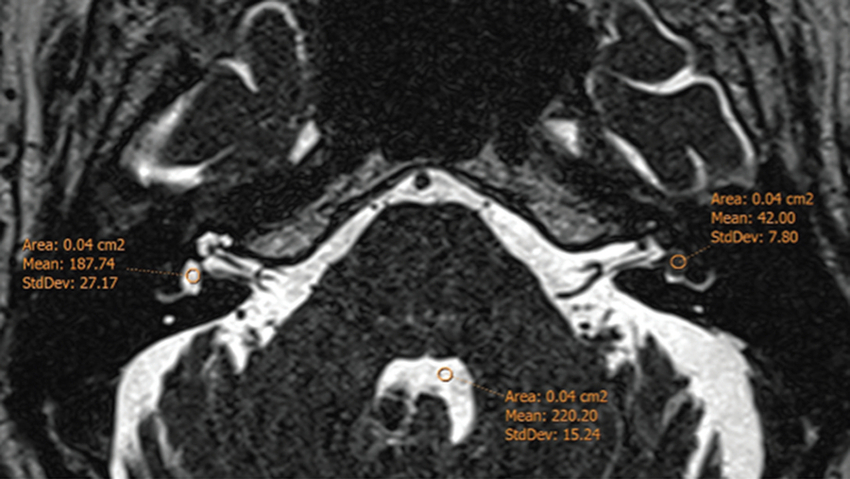

Se dibujaron áreas de interés (ROI, regions of interest) sobre la cóclea y el vestíbulo de ambos lados en las tres secuencias realizadas. Las mediciones fueron realizadas por un investigador con 6 años de experiencia en neuroimágenes (MPA). Los datos fueron estandarizados en relación con la señal del líquido cefalorraquídeo (LCR) del cuarto ventrículo para evitar variabilidad por diferencias en el fabricante del resonador (Fig. 1).